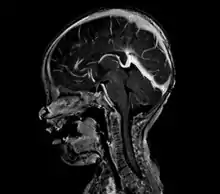

Vein of Galen thrombosis from ventricular puncture, not to be mistaken for an aneurysmal malformation

An AVM diagnosis is established by neuroimaging studies after a complete neurological and physical examination.[4][9] Three main techniques are used to visualize the brain and search for AVM: computed tomography (CT), magnetic resonance imaging (MRI), and cerebral angiography.[9] A CT scan of the head is usually performed first when the subject is symptomatic. It can suggest the approximate site of the bleed.[2] MRI is more sensitive than CT in the diagnosis of AVMs and provides better information about the exact location of the malformation.[9] More detailed pictures of the tangle of blood vessels that compose an AVM can be obtained by using radioactive agents injected into the blood stream. If a CT is used in conjunctiangiogram, this is called a computerized tomography angiogram; while, if MRI is used it is called magnetic resonance angiogram.[2][9] The best images of an AVM are obtained through cerebral angiography. This procedure involves using a catheter, threaded through an artery up to the head, to deliver a contrast agent into the AVM. As the contrast agent flows through the AVM structure, a sequence of X-ray images are obtained.[9]